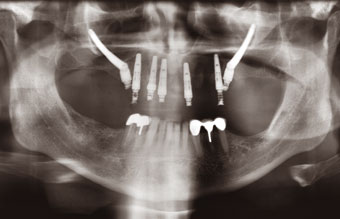

In a “first of its kind” procedure in the South East, Oral surgeon Guy Barwell placed two zygoma dental implants alongside five standard implants, which were immediately loaded by The Implant Centre resident Specialist Prosthodontist, Jonathan Murphy. The patient had been referred to the centre with failing bridges and crowns in his maxilla. Following his consultation he decided to undergo an upper clearance and a denture was fitted. After an initial healing period, the implants were placed and immediately restored with the patient under sedation. The patient returned home that morning with a fixed bridge. In three months time this will be restored with a definitive titanium bridge… a time saving of nine months.